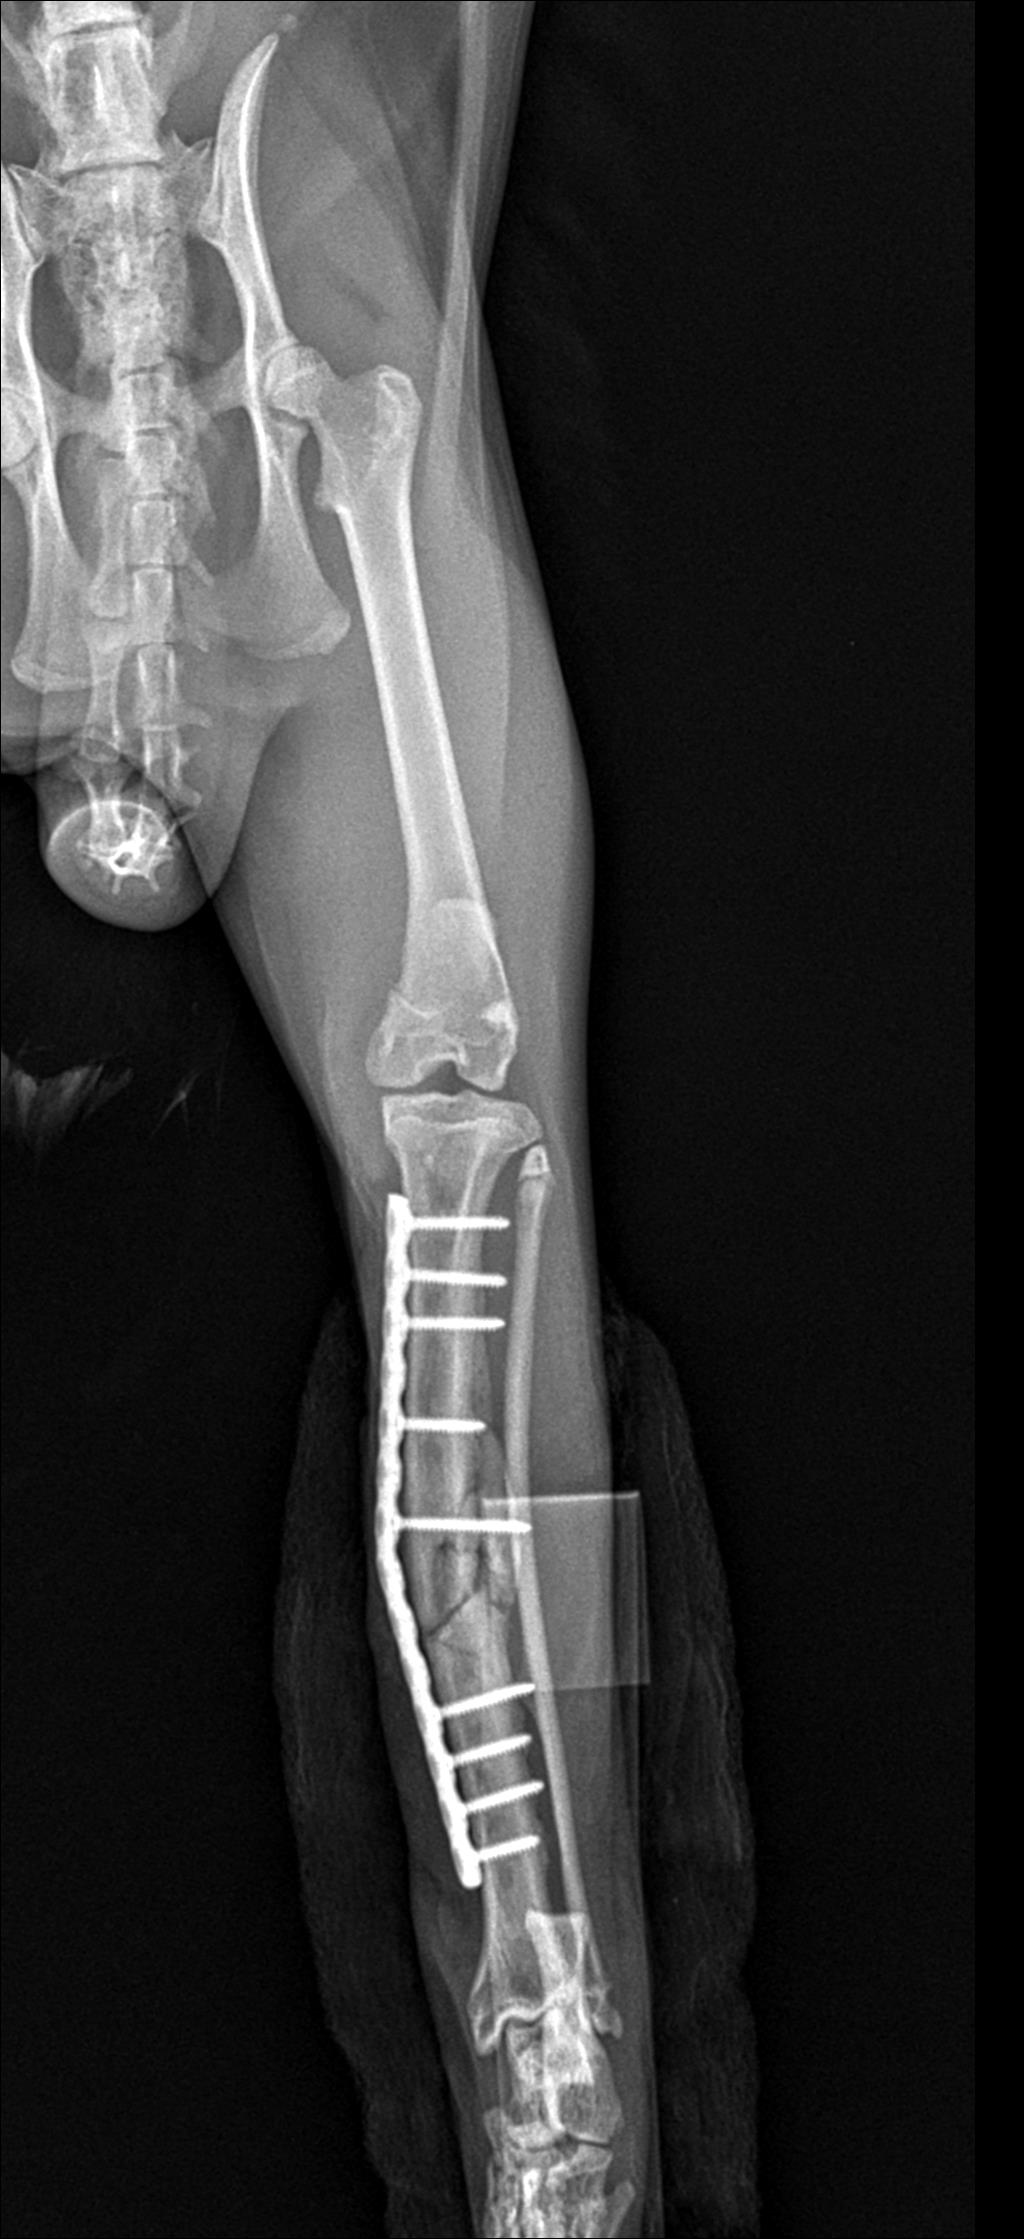

그렇게 2달여간의 치료 끝에 붕대를 풀게 되었고 그 사이에 예방접종과 동물 등록을 함께 진행하였습니다.

현재 붕대를 풀었으나 높은 곳으로 이동하지 않도록 주의 깊게 지켜보며 보호중입니다.

골절 수술과 예방 접종 3회가 끝나 현재는 실내에서 다른 고양이들과 지내고 있습니다. 현재 임시 보호중이고 입양을 알아보고 있습니다. 다람이가 아직 나이가 어리고 온순한 성격이라 다른 고양이들과의 합사도 원만하게 진행되었고 만져주는 것을 좋아해서 사람도 잘 따릅니다. 다른 전염병이나 아픈 곳은 없고 식사도 잘하고 터널과 캣타워를 좋아하는 캣초딩입니다.